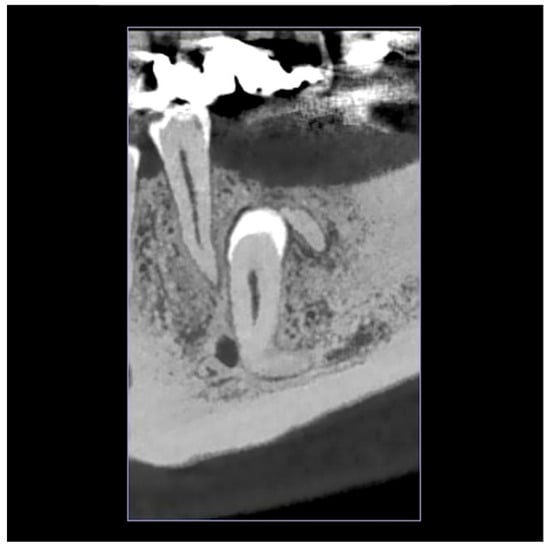

2.1. Initial Visit, Radiographic Evaluation and Diagnosis